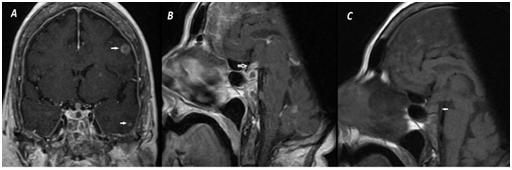

However, suspected diagnosis was DI because of sustained high dilute urinary output although obtained normoglycemia and persistent hypernatremia resistant to fluid replacement. Sella magnetic resonance imaging (MRI) was performed because of metastatic malignancy in history. Neurohypophysis high signal intensity loss secondary to stalk invasion in T1 weighted imaging (T1WI), stalk thickening and diffuse contrast distribution with contrasted T1WI, diffuse nodular contrasted focus due to intracerebral metastasis was showed (Figure 2). General condition of the patient was not suitable for water deprivation test. Therefore, desmopressin acetate treatment was started empirically; then urinary output improved and plasma Na concentrations was between 140-145 mg/dl.

Figure 2 A: In contrasted coronal and sagital T1WI stalk thickening and diffuse contrast involvement (open white arrow).

B: Accompanying diffuse nodular contrasted intra cerebral metastatic focus (closed white arrow).

C: In sagital T1WI signal intensity loss secondary to neuro hypophysial stalk invasion (closed white arrow)